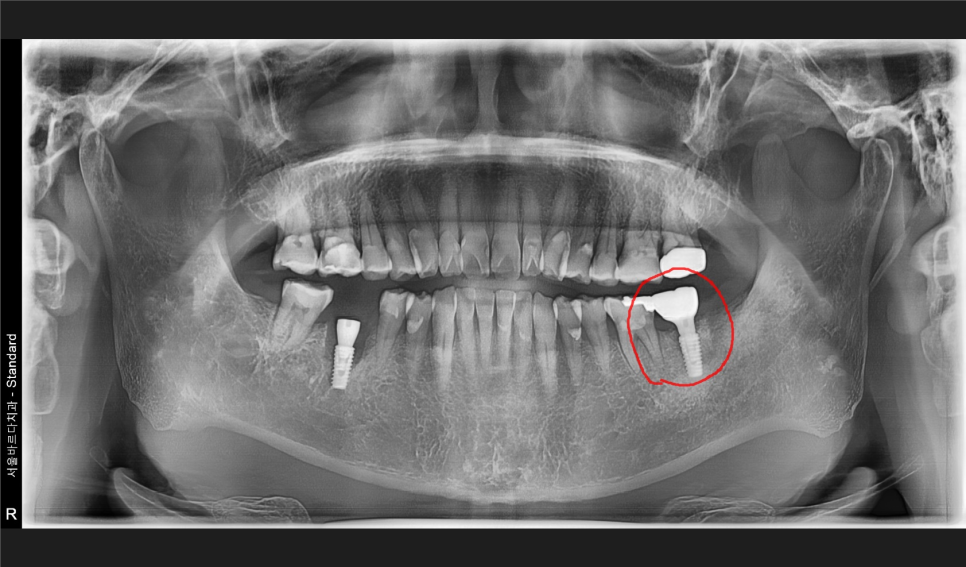

먼저 치과치료의 가장 기본에 해당하는 X-ray들을 보겠습니다.

어금니에 잇몸이 안좋아보이는 부분들이 몇군데 보이는군요.

자세히 보는 작은 X-ray를 추가로 촬영합니다.